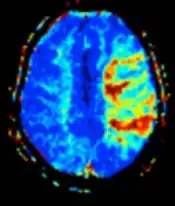

| Perfusion weighted (PWI) | Dynamic susceptibility contrast | DSC | Measures changes over time in susceptibility-induced signal loss due to gadolinium contrast injection.[23] |

|

![]() |

- Dynamic susceptibility contrast (DSC): Gadolinium contrast is injected, and rapid repeated imaging (generally gradient-echo echo-planar T2 weighted) quantifies susceptibility-induced signal loss.[45]

The acquired data is then postprocessed to obtain perfusion maps with different parameters, such as BV (blood volume), BF (blood flow), MTT (mean transit time) and TTP (time to peak).

In cerebral infarction, the penumbra has decreased perfusion.[24] Another MRI sequence, diffusion-weighted MRI, estimates the amount of tissue that is already necrotic, and the combination of those sequences can therefore be used to estimate the amount of brain tissue that is salvageable by thrombolysis and/or thrombectomy.